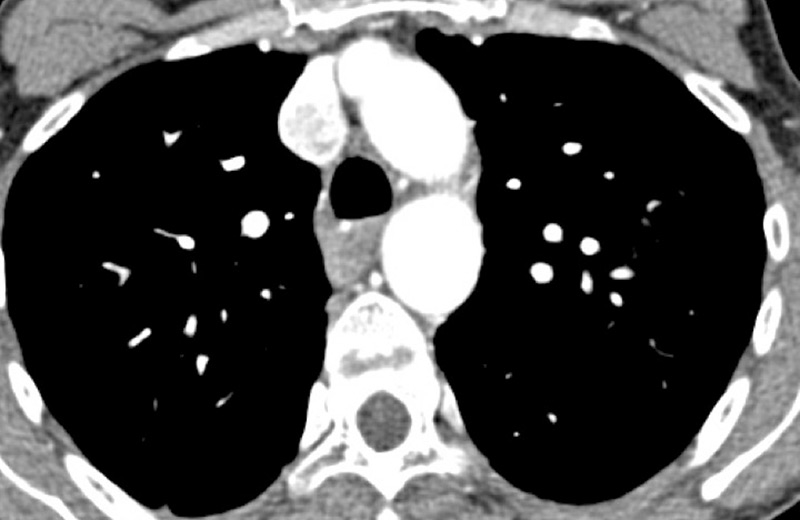

Figure 4

Peripheral chronic thromboembolic pulmonary hypertension (CTEPH). No visible pulmonary artery emboli on standard CTPA are seen (arrows) (A) but a wide perfusion defect on the perfusion maps is depicted (B) and allows the diagnosis of peripheral CTEPH.